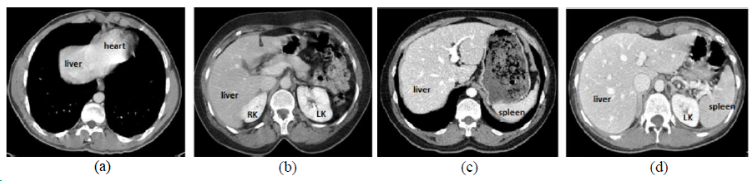

chaos.png